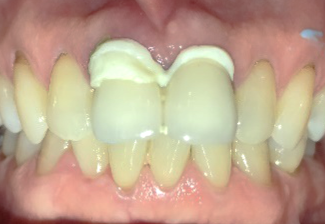

前歯2本を抜歯し、同時に骨造成をしました。骨ができる期間を約5か月待ち、インプラントを2本埋入しました。

所感

インプラント治療を希望し、函館から車で1時間10分ほどかかる江差町の歯科医院から、紹介されて来院されました。前歯2本は、歯根が破折していました。歯根の割れ方が、小さければ抜歯せず保存できる場合がありますが、この症例は真っ二つに割れていましたので抜歯せざるを得ませんでした。

抜歯前に、抜歯後の治療法について詳しく説明したところ、インプラント治療を希望されました。歯根が破折した状態で、1年以上経過していましたので、歯根の周りの骨が大きく欠損していることがわかりましたので、抜歯と同時に骨造成をすることを計画しました。抜歯と骨造成後、5か月を待ち、X-Guideを使用し、正確にインプラントを埋入しました。

Before

After